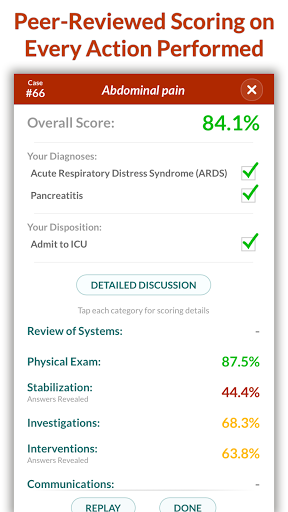

• Điểm số chi tiết và phân tích toàn bộ trường hợp - tìm hiểu điểm mạnh và điểm yếu của bạn

Các trường hợp có thể lặp lại vô hạn của Full Code đo lường các kỹ năng trong cả chẩn đoán và quản lý, cho phép bạn học hỏi từ những sai lầm của mình trong một môi trường không có rủi ro. Xây dựng năng lực để bạn có thể đối mặt với các trường hợp thực tế phức tạp một cách tự tin.